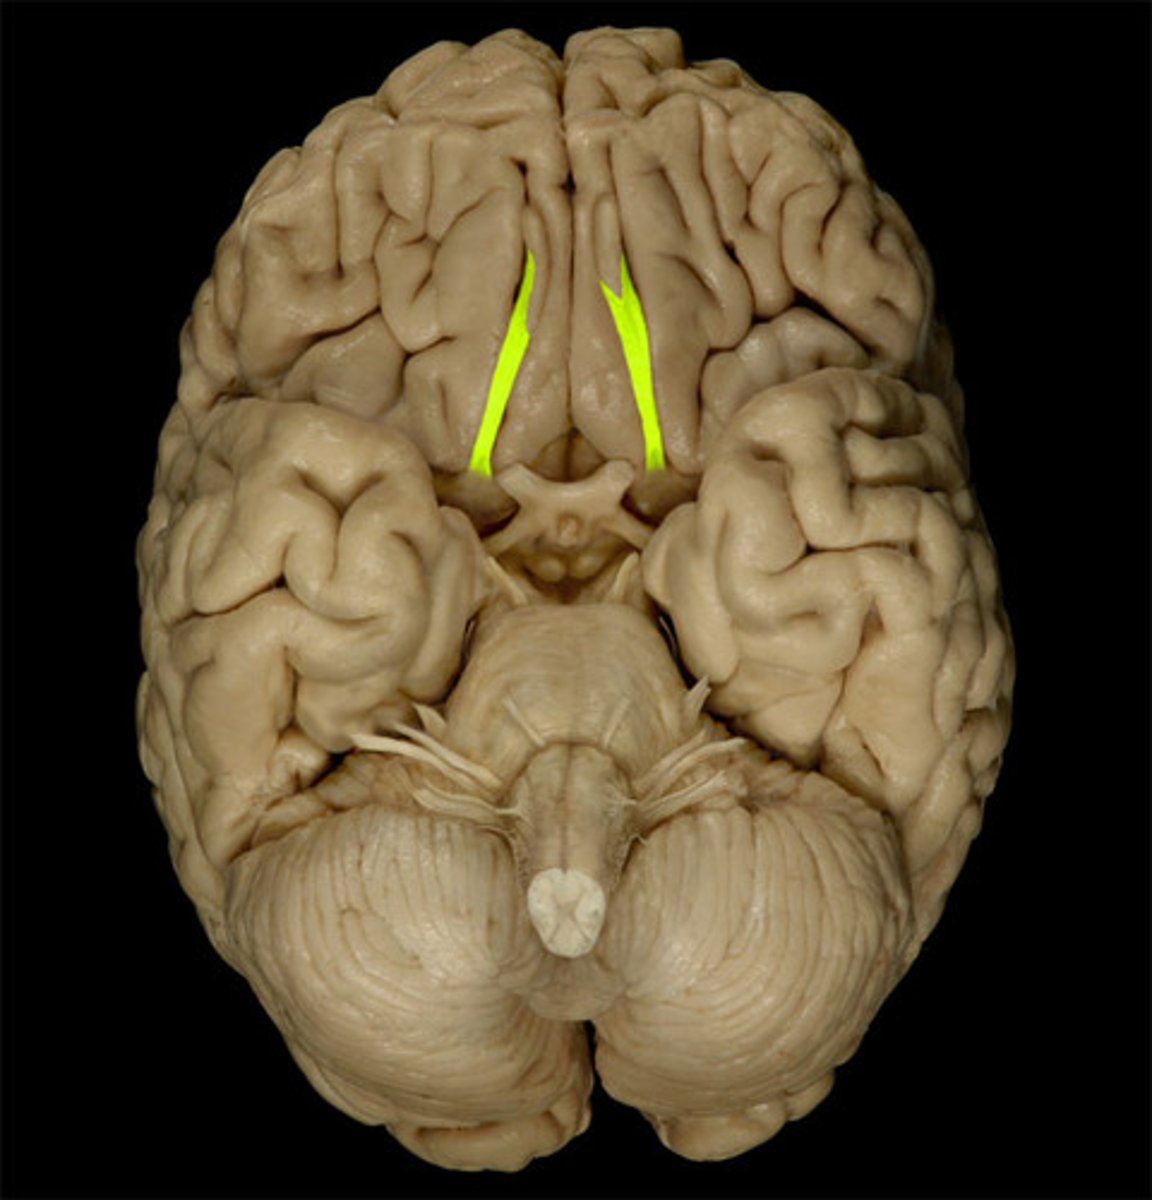

optic nerve (CN II)

Sensory cranial nerve related to vision

optic chiasm

point at which optic nerve fibers cross in the brain

optic tracts

the continuation of the optic nerve fibers beyond the optic chiasma

primary visual cortex

•Located within occipital lobe; receives, processes, stores visual information